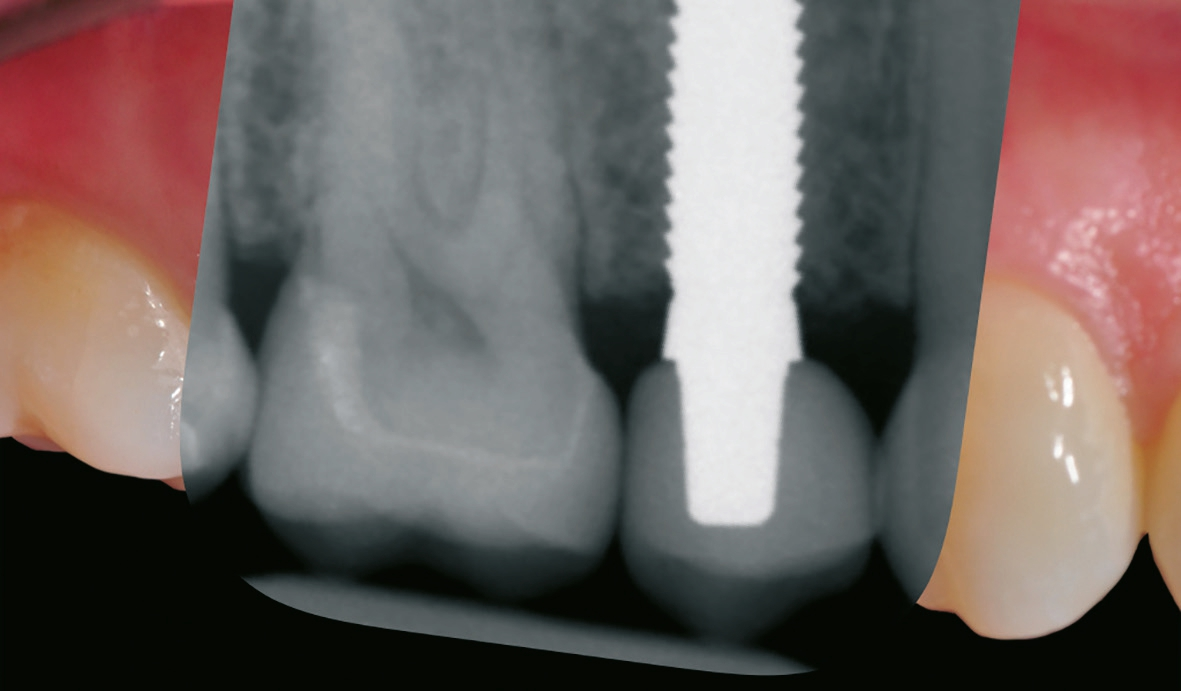

Nach sorgfältiger Kürettage und Inspektion einer idealen Knochenalveole vom Typ I [11] konnte mit der Sofortimplantation begonnen werden. Die ersten beiden Pilotbohrungen wurden teilnavigiert mit der Bohrschablone durchgeführt. Das restliche Bohrprotokoll wurde nach den Vorgaben des Herstellers frei durchgeführt. Mit der Insertion des Implantats konnte die nötige Primärstabilität von 35 Ncm für eine sofortige provisorische Versorgung erreicht werden. Im Vorfeld war ein Situationsmodell der Ausgangssituation und darauf eine Tiefziehschiene vorbereitet worden, die jetzt für die intraorale Herstellung des Provisoriums mit fließfähigem Kompositmaterial verwendet wurde. Als stabilisierende Gerüststruktur diente dabei die präzise sitzende Einbringkappe (insertion.transfer) auf dem Implantatkopf, die zuvor auf die entsprechende Höhe eingekürzt worden war. Nach der Ausarbeitung und okklusalen Adjustierung der Krone wurde diese provisorisch zementiert.

Nach einer komplikationsfreien Einheilzeit von vier Monaten konnte mit der Herstellung des definitiven Zahnersatzes begonnen werden. Hier entschied man sich konsequent für monolithische Kronen aus Lithiumdisilikat, um das Chippingrisiko so gering wie möglich zu halten [12]. Im Zuge der Implantatversorgung wurde nun auch – wie geplant – die metallkeramische Krone an 16 geschlitzt, entfernt und der Stumpf nachpräpariert. Implantatkopf und Zahnstumpf wurden daraufhin zusammen mit A-Silikon analog abgeformt. Für die geschlossene Abformung wurde die Abformkappe (impression.transfer) auf dem Implantatkopf positioniert. Ein deutliches Einrasten signalisierte den lagestabilen Sitz. Für die Modellherstellung rastete das Implantatanalog (lab. replica) ebenso in die integrierte Abformkappe ein. Nach der Herstellung des Meistermodells konnten die beiden Kronen im digitalen Workflow CAD/ CAM-gestützt gefertigt werden. Nach Ausarbeitung, Bemalung und Glasur waren die beiden Kronen für die definitive Zementierung bereit. Die klinische Einprobe der Restaurationen verlief erfolgreich, sodass die Kronen nacheinander mit selbstadhäsivem Befestigungskomposit eingegliedert werden konnten.